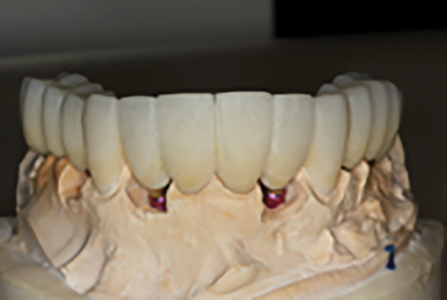

This case was chosen to demonstrate how a fixed transitional prosthesis using hopeless teeth and tooth roots can provide a smooth transition to the definitive prostheses. This is a divergence from the ‘Convenient Engineering’ approach often used in implant dentistry, but was conceived with the patient’s best interest in mind. The patient were given alternative options including hybrid-type immediate prostheses, bar over-dentures and conventional maxillary and mandibular complete dentures but chose this alternative because of stable provisionals with ‘a no rush to finish’ approach and because of the progressive transitioning from the natural dentition to the definitive implant prostheses.

Bis-bake for try-in

Immediate insert

The before compared to the one-month post-op

Abutment try-in

One-month post-op